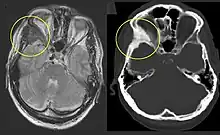

On x-ray, fibrous dysplasia appears as bubbly lytic lesions, or a ground glass appearance. Computerized tomography (CT) or magnetic resonance imaging (MRI) scans may be used to determine how extensively bones are affected. CT can better demonstrate the typical "ground glass" appearance, which is a highly specific radiological finding, while MRI can show cystic areas with fluid contents.[18] A bone scan uses radioactive tracers, which are injected into the bloodstream. The damaged parts of bones take up more of the tracer, which show up more brightly on the scan. A biopsy, which uses a hollow needle to remove a small piece of the affected bone for laboratory analysis, can diagnose fibrous dysplasia definitely.